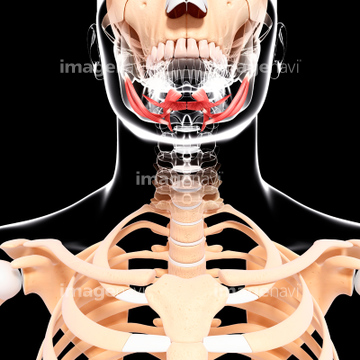

下顎骨 Mandibula 顔面最下部にある顔面骨中、最も強大な骨。 頭蓋と関節で連結するただ1個の骨で、側頭骨と顎関節をつくります。 下顎骨は下顎体と下顎枝に分けられる。 下顎体の上面は歯槽部で下顎の歯を入れる16個の歯槽を有する。 下縁正中部は前下方に突出し人類に特有のオトガイをつくる。 内面正中にオトガイ棘、その下外側に二腹筋窩がある。 ここ 1骸骨のような顔になる原因top 2。 1目の周りがこける。 2頬がこける。 このように、顔の上の皮膚がこけ、垂れる事により骸骨のような顔になる事は間違いないでしょう。 それぞれの原因と、その対処法を考えていきましょう。永久歯の中で最も早く生えてくる第一大臼歯や前歯は妊娠3~5ヶ月頃に歯胚ができ、時間をかけて成長していきます。 生えかわりが始まる6歳頃には、あごの中で生える準備をしています。 2 永久歯へ生えかわる仕組み 1 顎の中 (乳歯の下)で永久歯のもと

歯の痛み 虫歯ではない歯の痛みを引き起こす時は、頭蓋骨の歪みを矯正すると改善する場合があります。 顎関節症 顎関節症は顎の問題だと思われていますが、顎が引っかかっている頭蓋骨の問題でもあります。サイズ:21×15×18CM 重量:08~1KG 材質:PVC *裂、孔、各窩、隆起、突起、縫合線を忠実に再現する。 *頭蓋冠、頭蓋底、下顎の3つのパーツ構成。 頭蓋冠は取り外し可能です。 *歯が取り外し可能です。 替え歯も付属。 *顎関節は開閉可能、実際の顎関節の頭蓋骨;ズガイコツ 解剖学 頭蓋;ズガイ 新生児 頭蓋泉門 頭蓋:解剖図 骨口蓋 頭蓋腔 頭蓋の縫合 内頭蓋底 上面観;上面概観 外頭蓋底 底面観;外頭蓋底 眼窩 眼窩 , 鼻腔 前面観